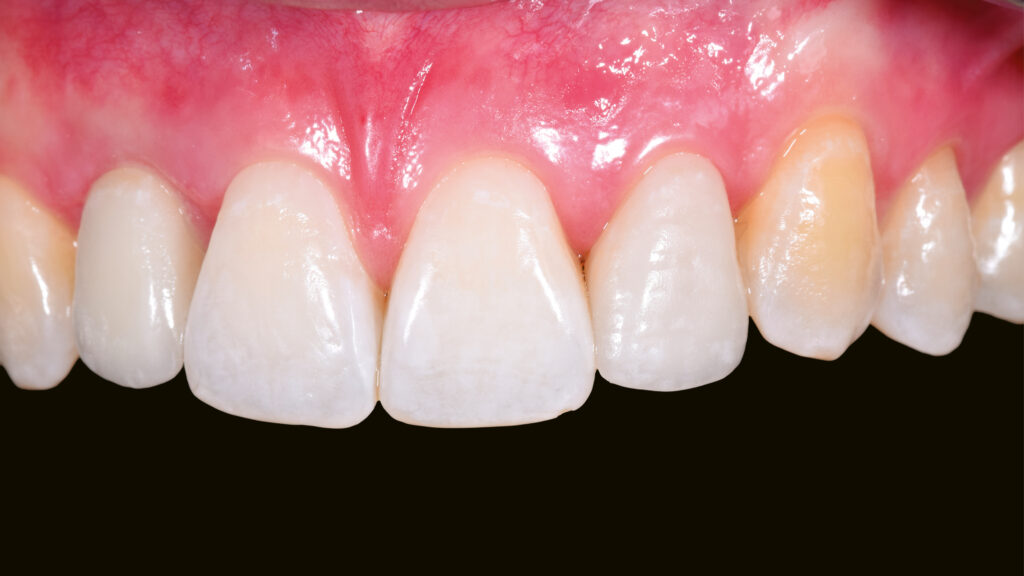

Nach der Heilung des Weichgewebes sind die arkadenförmige Kontur der Gingiva und die Papillen deutlich zu erkennen (Abb. 42 und 43). Etwa sechs Monate nach der Osseointegration und Konditionierung der Gingiva wird die Situation mit dem Intraoralscanner erfasst, um mit der Herstellung der implantatprothetischen Versorgung fortzufahren. Nach dem Aufschrauben des Scanbodys auf das Implantat erfolgt der Scanvorgang (Abb. 44). Intraoralscanner gehören zu den aufregendsten neuen Technologien in der Zahnmedizin. Die digitale Abformung bietet dem Patienten deutlich mehr Komfort. Zudem werden klinische Abläufe vereinfacht und die Kommunikation mit dem Zahntechniker verbessert. Im nächsten Schritt werden die STL-Dateien für den Modelldruck aufbereitet (Abb. 45). Vor dem Scannen der gedruckten Modelle muss das Modellanalog regio 12 eingesetzt werden. Das Modell mit abnehmbarer Gingivamaske ist für die Aufnahme des Modellanalogs durch eine Öffnung vorbereitet und besitzt im unteren Bereich des Ausschnittes eine Art Verriegelungsmechanismus (Abb. 46). Dies gewährleistet einen sicheren Presspassung und eine korrekte, automatisch zentrierte Einschubposition (Abb. 47).

Die Gestaltung des marginalen Randes („Präparationsrand”) im bukkalen Bereich erfolgt in Absprache mit dem Zahnarzt ca. 0,2 mm subgingival (Abb. 52). Palatinal endet die Verblendkeramik supragingival, um hier die biologischen Vorteile des Zirkonoxids zu nutzen (Weichgewebekonditionierung) (Abb. 53). Vor allem im Frontzahnbereich wird das individualisierte Emergenzprofil als wichtiger Faktor für die Rekonstruktion einer zufriedenstellenden Ästhetik angesehen. Zudem werden im Frontzahnbereich mit Zirkonoxid biologisch und ästhetisch bessere Ergebnisse erzielt als mit Titan, das bei dünnem Gingiva-Biotyp durchscheinen kann (Abb. 54 und 55).

Eingliederung der Implantatkrone

Nach einigen Monaten war das periimplantäre Weichgewebe endgültig stabilisiert. Es zeigte sich noch eine leichte Narbenbildung am Gingivazenit. Nach vorsichtigem Ausdrehen der provisorischen TempShell-Krone offenbart sich eine gut ausgebildete Weichgewebsarchitektur. Die Gewebedicke an der Implantationsstelle ist vergleichbar mit der Situation am zu kopierenden linken lateralen Schneidezahn (Abb. 64). Die Zirkonoxidkrone mit Titanadapter wird definitiv mit dem Implantat verschraubt. Durch die detaillierte digitale Vorbereitung sind oft nur kleine Korrekturen notwendig. Meist können die Restaurationen ohne Einprobe eingegliedert werden. Die biokompatiblen Anteile der Implantatkrone (Titanadapter) und die subgingivalen Anteile der Implantatkrone gewährleisten eine optimale Anlagerung der Gingiva (Abb. 65). Der spaltfreie Sitz der Versorgung auf dem Implantat wird röntgenologisch kontrolliert.

Abschließend kann der Schraubenkanal mit Teflonband und Komposit verschlossen und die statische und dynamische Okklusion überprüft werden. Bei der Eingliederung einer Frontzahnimplantatkrone kommt es vor allem auf eine ästhetische Integration an. Neben der weißen Ästhetik ist die rote Ästhetik mit der Ausformung des Emergenzprofils und der Harmonie des Gingivaverlaufs wichtig. Die Restauration fügt sich ästhetisch gut in die Zahnreihe ein (Abb. 66 bis 68). Das Zusammenspiel der dentalen und gingivalen Umgebung sowie der Lippen mit der prothetischen Versorgung ergibt ein harmonisches Gesamtbild (Abb. 69). Einige Monate nach dem Einsetzen der Implantatkrone hat sich die Gingiva sichtbar gut erholt (Abb. 70).